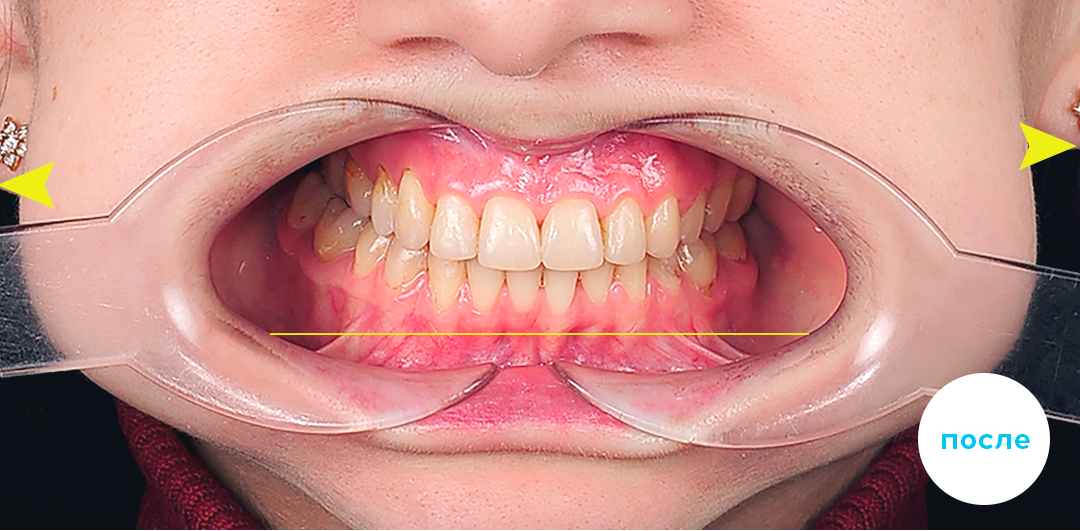

До

После

Глубокий прикус